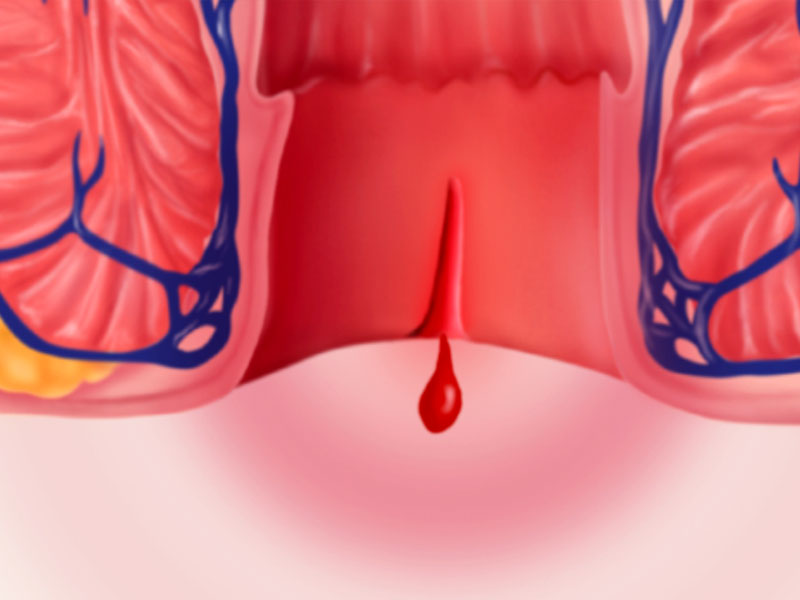

Anal Fissure

Simply put, a fissure is a cut in the anal canal. Because it's richly innervated with sensory pain fibers, a fissure is often very painful.